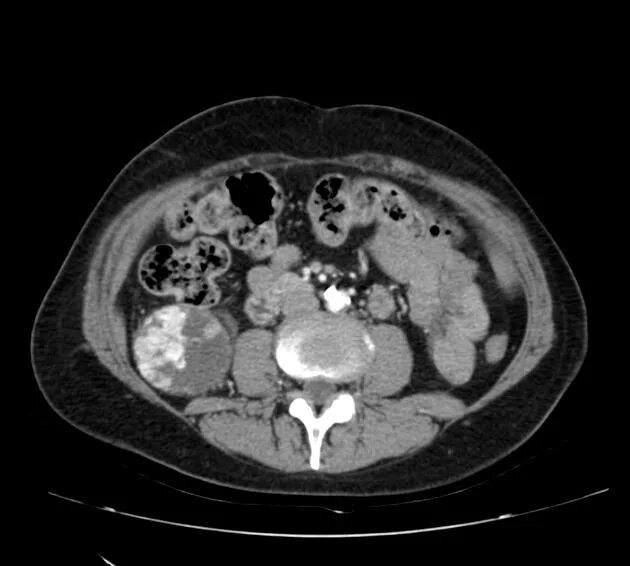

Кисты почек bosniak